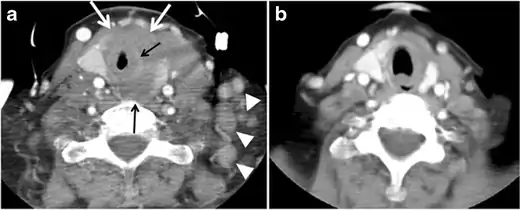

The radiologist must evaluate the central structures draping the thyroid gland including the trachea, oesophagus, larynx, and pharynx, as well as the recurrent laryngeal nerve. Invasion is suspected if the thyroid mass abuts the airway or oesophagus for more than 180 degrees. Luminal deformity, mucosal thickening and mucosal focal irregularity are more specific indicators of invasion. Obliteration of the fat planes of the tracheoesophageal groove in three axial images and signs of vocal cord paralysis are indicative of recurrent laryngeal nerve invasion. Invasion of these central structures meets the criteria for T4a disease (Figs. 5 and and6)6).[1]

Arterial invasion constitutes T4b disease, which may preclude curative surgery. More than 180 degrees of arterial encasement is suggestive of invasion, however, arterial deformity or narrowing is much more suspicious for invasion. The carotid artery is the most commonly involved artery; however, the mediastinal vessels should also be examined. Encasement of the carotid artery or mediastinal vessels for more than 270 degrees is unlikely to be resectable. On the other hand, occlusion or effacement of the internal jugular vein can occur without invasion and does not influence surgical resectability or staging. Asymmetry of the strap muscle and the tumour abutting its external surface are signs of an invasion. However, invasion of the pre-vertebral musculature is more challenging, as a large lesion can compress the muscle without invasion (Figs. 5 and and6)6).[1]

Finally, the possibility of metastatic disease should be excluded. PTCs and medullary thyroid carcinomas tend to metastasize to regional lymph nodes. According to the AJCC/UICC TNM staging system, the nodal stage is classified by site: N1a indicates level VI nodal involvement, including paratracheal nodes; N1b indicates unilateral or bilateral lateral cervical nodal disease or superior mediastinal nodal disease (Figs. 4, 55 and and6)6).[1]